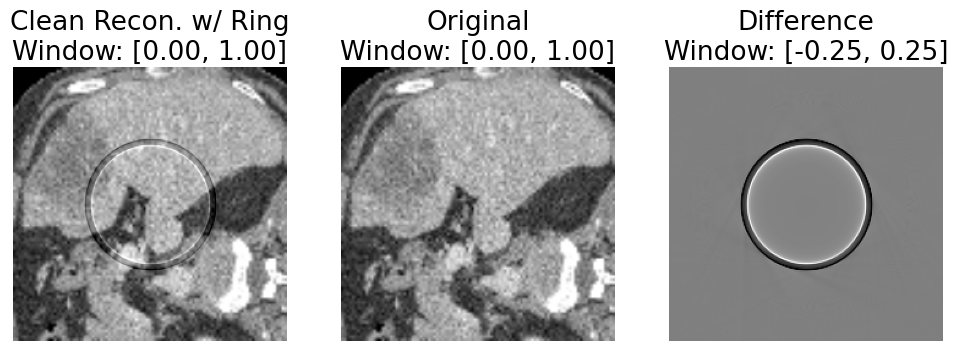

Refer to caption

Figure 4. Result of our proposed approach to addressing error introduced by simulating artifacts with forward and backprojection. Leftmost image is OdistortedO_{distorted}, middle is OO, right is OdistortedOO_{distorted}-O. There is no longer a visible difference between the distorted image OdistortedO_{distorted} and OO aside from the ring artifact; this makes OdistortedO_{distorted} a reasonable depiction of OO with the ring artifact, and without error introduced by forward and backprojection. For ease of visualization, we simulate 5 adjacent detector channels with gain error -10%.

See Fig. 4 for an example following those used in discussion thus far, in which 10% gain error is simulated on 5 adjacent detector channels to make the ring easier to distinguish from anatomy for discussion’s sake. See Fig. 5 for an example of the actual ring distortion we used in our experiments, which applies up to 10% gain error to all simulated detectors.